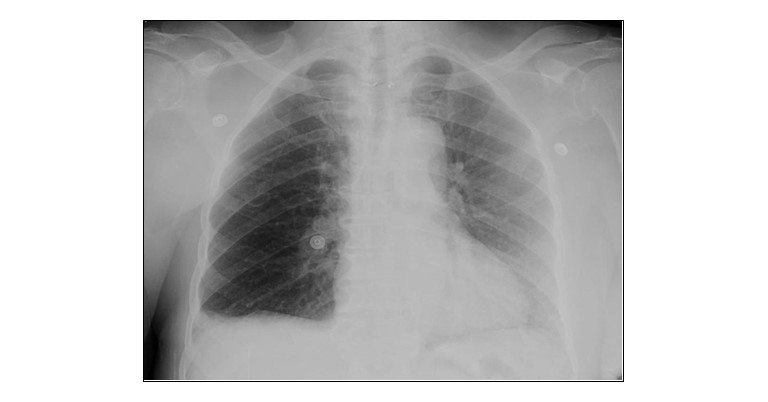

X-Ray chest PA view